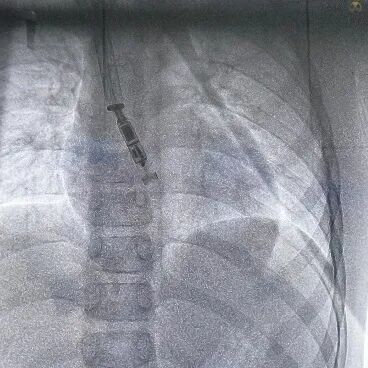

手术在全麻下进行,在超声引导下成功穿刺右侧颈内静脉,置入8F鞘管并提前置入Proglide血管缝合器。经鞘管送入导丝,稳定通路后,将Micra AV递送系统沿导丝轻柔推进,经上腔静脉、右心房进入右心室。术中采用多角度X线透视(LAO 30°、RAO 30°)及心腔内超声(ICE)辅助,精确引导递送系统定位至右室间隔中位。

在确认器械锚定满意,进行电参数测试。结果显示起搏阈值0.5V @ 0.24ms,感知振幅7.7mV,阻抗740 Ω,各项参数均理想。完成测试后释放起搏器,牵拉试验确认固定稳定,手术顺利完成,总操作时间35分钟,无并发症发生。

提前置入 Proglide 血管缝合器